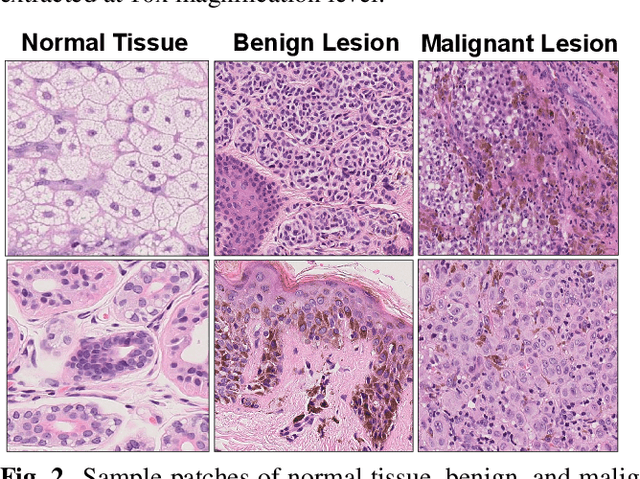

Melanoma diagnosed and treated in its early stages can increase the survival rate. A projected increase in skin cancer incidents and a dearth of dermatopathologists have emphasized the need for computational pathology (CPATH) systems. CPATH systems with deep learning (DL) models have the potential to identify the presence of melanoma by exploiting underlying morphological and cellular features. This paper proposes a DL method to detect melanoma and distinguish between normal skin and benign/malignant melanocytic lesions in Whole Slide Images (WSI). Our method detects lesions with high accuracy and localizes them on a WSI to identify potential regions of interest for pathologists. Interestingly, our DL method relies on using a single CNN network to create localization maps first and use them to perform slide-level predictions to determine patients who have melanoma. Our best model provides favorable patch-wise classification results with a 0.992 F1 score and 0.99 sensitivity on unseen data.